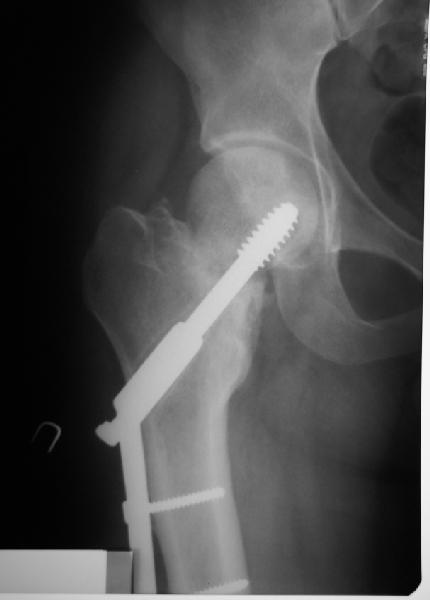

Пациент 20 лет  по поводу перелома шейки бедра оперирован в соседнем регионе 9 мес. назад.

На сегодня такая картина. Ходит с тростью, боли практически нет. Направили для эндопротезирования. У нас намерения больше в сторону вальгизируюещей остеотомии. То ли потом фиксировать как есть, то ли на уровне несращения шейки что-то подправить. Какие будут предложения?